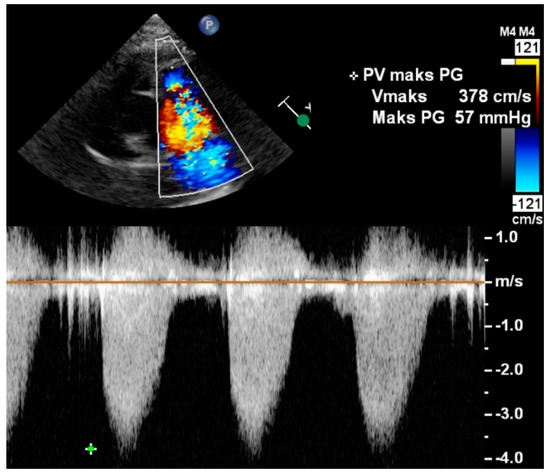

- Hioka, T.; Kaga, S.; Mikami, T.; Okada, K.; Murayama, M.; Masauzi, N.; Nakabachi, M.; Nishino, H.; Yokoyama, S.; Nishida, M.; et al. Overestimation by echocardiography of the peak systolic pressure gradient between the right ventricle and right atrium due to tricuspid regurgitation and the usefulness of the early diastolic transpulmonary valve pressure gradient for estimating pulmonary artery pressure. Heart Vessels 2017, 32, 833–842. [Google Scholar] [PubMed]